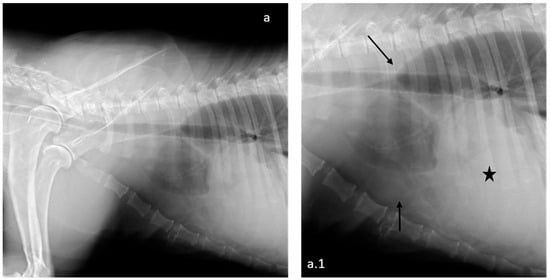

2.1. Clinical Report

2.2. Gross Pathology